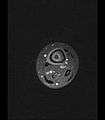

Axial T1-weighted MRI pre-contrast enhancement showing that the intramedullary collection is T1-hyperintense suggesting proteinaceous viscous fluid consistent with infection.